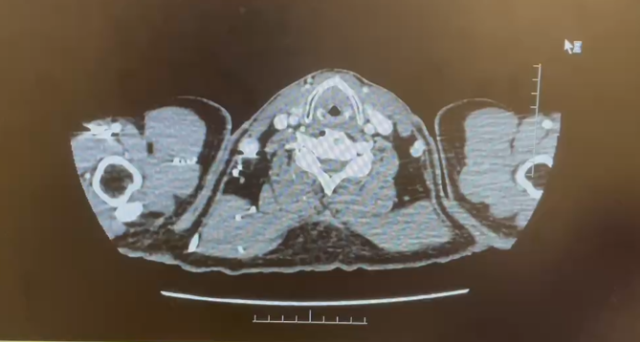

CT 报告

1.下腔静脉管腔较前缩小、充盈缺损较前减少;

2.右肾静脉栓子较前减少;右侧髂总静脉内少许栓子;

3.右肾上极病变较前缩小,右肾孟管壁受累较前减轻;

4.盆腔少量积液较前减少;

5.左下肺动脉栓子形成,范围较2024-01-22日稍缩小;

6.左肺上叶结节较前稍增大,性质待定;

7.双肺下叶少许条索较前减少。

日期:2024.3.21

直接减影血管成像

1. 下腔静脉管腔较前缩小、充盈缺损较前相仿;

2. 右肾静脉、右侧髂总静脉栓子较前减少;

3. 右肾上极病变较前缩小,右肾盂管壁受累较前相仿;

4.盆腔积液现已吸收;

5.左下肺动脉栓子较前相仿;

6. 左肺上叶结节较前相仿;

7.双肺下叶少许条索较前减少

日期:2024.4.30